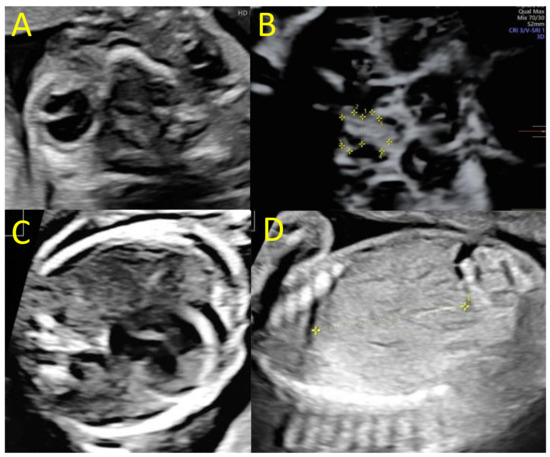

3. Case Report